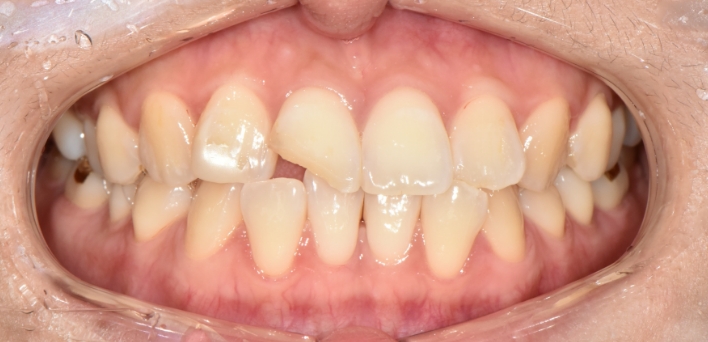

※ 더서울치과의원은 의료법을 준수하며 위 케이스는 실제 환자의 동의를 얻은 사례로 치료 전, 후가 동일한 환경에서 촬영되었습니다.

환자 케이스에 따라 부작용이 발생할 수 있습니다. 이 부분은 의료진의 충분한 상담과 체크를 통해 예방하고 줄일 수 있습니다.

[심미치료 부작용] 시술 후 치아 시림, 보철물 파손 등의 부작용이 발생할 수 있어 개인별 치아 상태에 따른 정확한 진단과 사후 관리가 중요합니다.